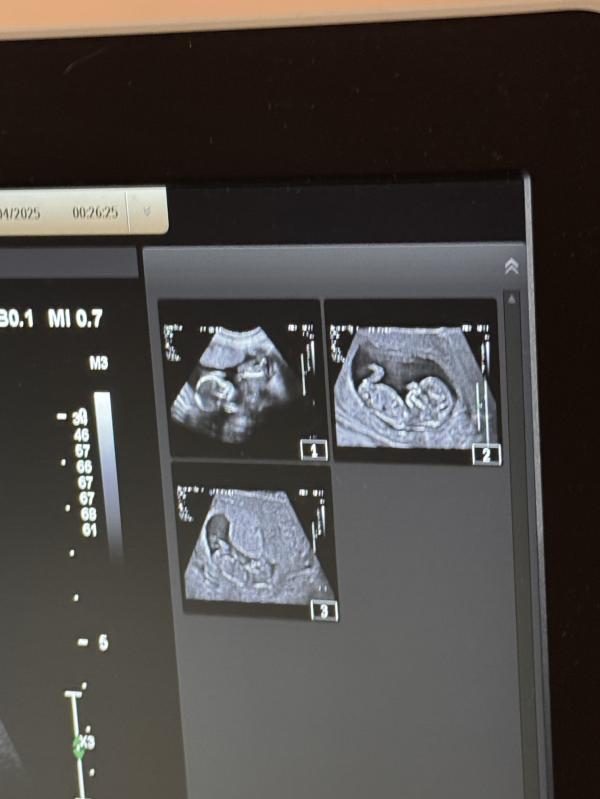

Я сходила на первый скрининг, очень порадовалась, что срок по месячным 100% совпадает со сроком на узи ☺️

Все хорошо, креветочка 5,3см, всякие гадости и отклонения, к счастью, не обнаружены.